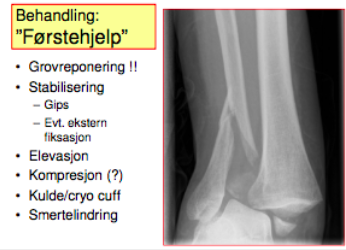

Man kan dele opp behandlingen av ankelskader i tre deler. forklar.

Kan bruke tape/elastiske bind.

Trening: 10 min daglig i 10 uker.

Hvordan reponere ankelbrudd?

Trenger ikke så mye smertestillende.

Legg hånden dere har bak calcaneus til å trekke talus fremover og dytte mot medialsiden.

Hold der mens dere gipser. 1 - 2 lag kalk-gips - U-laske rundt. Ta samme kompresjon som tidligere i gipsen.

Kirurgi innen 6- 8 timer?

Ellers til avsvelling noen dager - husk grovreponering.

Hvis pasienten kommer inn på natta - ofte bedre å vente.